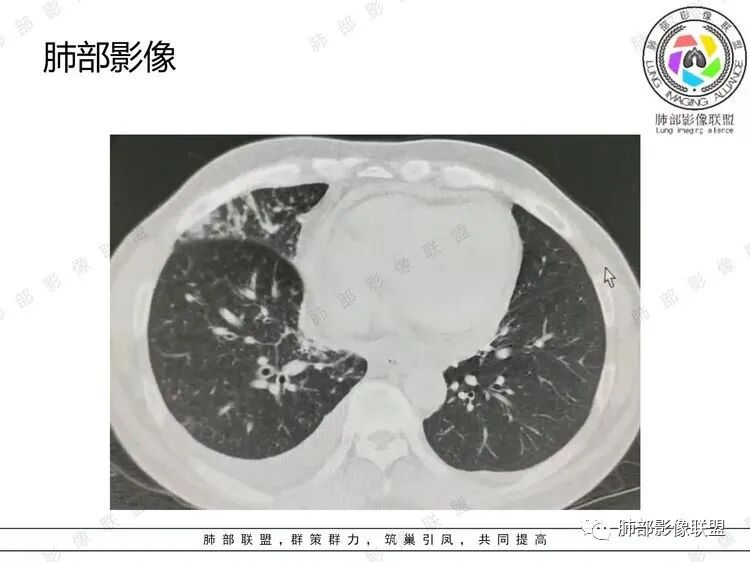

男,51岁,气促一月,发热半月,既往高血压病史及长期吸烟史。CT示右肺上叶沿支气管血管束分布多发小结节,叶间胸膜亦见,支气管壁增厚。纵隔、右肺门、膈上前组、腹膜后多发肿大淋巴结,部分融合成团,隆突下融合淋巴结内似见血管影,增强扫描轻度强化,胸腔积液及心包积液。综合考虑为淋巴瘤可能

B超:腹膜后淋巴结肿大。胸部CT:纵隔、右肺门多发肿大淋巴结,部分融合呈团块状,纵隔淋巴结有坏死,右肺多发中轴间质增厚及小叶间隔增厚,部分实变,沿支气管血管束分布有多发粟粒结节影,右侧胸腔积液,心包积液。

右肺上叶中轴间质增厚,周围可见边缘模糊片状影及多发小结节影,小叶间隔及叶间裂呈结节增厚,胸膜下多发结节影,纵隔及肺门多发淋巴结肿大,腹膜后淋巴结肿大,右侧胸腔积液,心包积液,考虑淋巴增殖性病变,1淋巴瘤2腺癌并癌淋。

右肺上叶沿血管支气管束分布的多发片状影,边界不清,血管束增厚相当明显。多发小结节影边界较清楚,胸膜下分布为主。

3.右肺上叶支气管壁广泛增厚,几乎累及所有分支。肺叶肺段支气管分支多处微小结节样突起,管腔不同程度狭窄,但未见阻塞,这在内窥镜下应当非常容易观察到。

5.右侧胸腔积液,右侧胸膜微小结节影,但胸膜未见强化结节影。